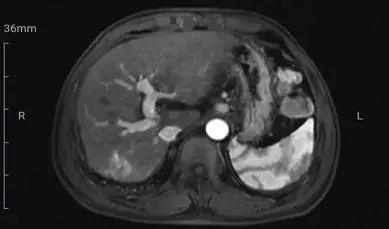

2019年9月6日复查肝功、肾功、血凝均正常;HBsAg 1786 IU/ml,HBeAg 7.74 IU/ml,hsHBV-DNA 10 IU/ml,AFP 15.97ng/ml。ECT:右侧第4、6、7肋骨及左侧第6肋骨代谢异常,建议随诊。上腹部MR增强:肝S7段可见动脉期明显结节样强化,门脉期及延迟期呈轻度强化灶(图1)。胸部增强CT: 左肺上叶1.5cm结节样高密度影,形态欠规则,边界清,增强扫描呈不均匀轻度强化。考虑肿瘤性病变:1. 原发支气管肺癌(小细胞肺癌)?2. 转移?(图2)。建议行肺穿刺活检或胸外科手术明确病灶性质,患者拒绝。

图1. 2019年9月5日腹部MR示肝S7段动脉期明显强化结节